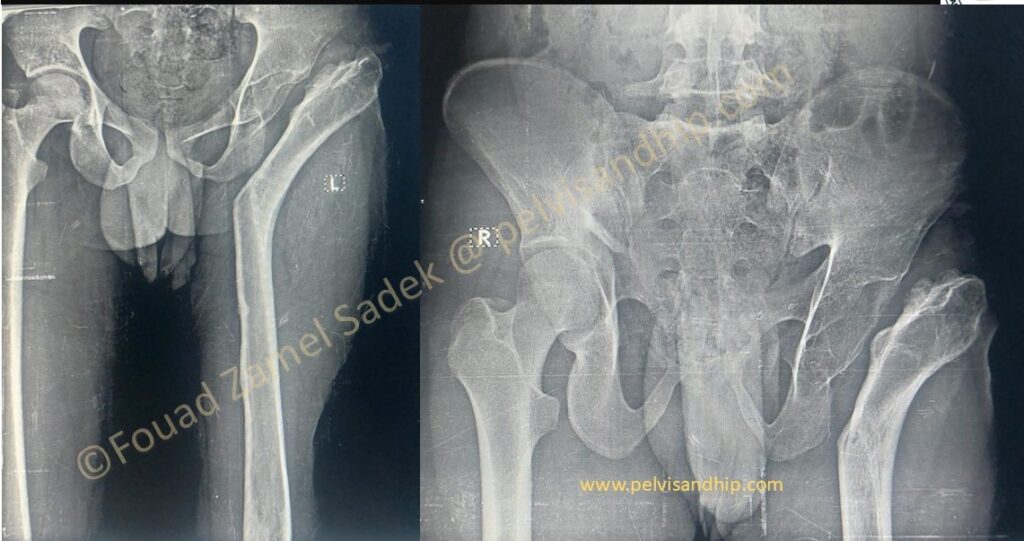

Story starts with a fall 7 years before with a resultant fracture neck of femur which was neglected. Patient states that he was treated with an application of some external fixation for a long time.

It is obvious that he had a Pelvic support osteotomy.

He is currently presenting with difficulty in walking, a significant pelvic tilt and leg length discrepancy. He gets early abductor weakness after any extended walking distance.

The obvious proximal femoral deformity can be clearly visualized on the 3D CT picture. The standing scanogram also shows the leg length discrepancy and the pelvic tilt. The insufficient adductor lever arm clearly explains the inadequate gait obtained from such a salvage procedure.